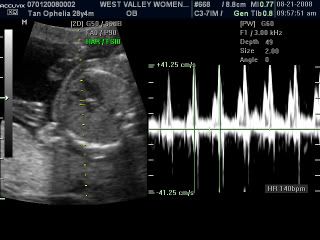

His heartbeat at 140bpm! Whoosh whoosh!